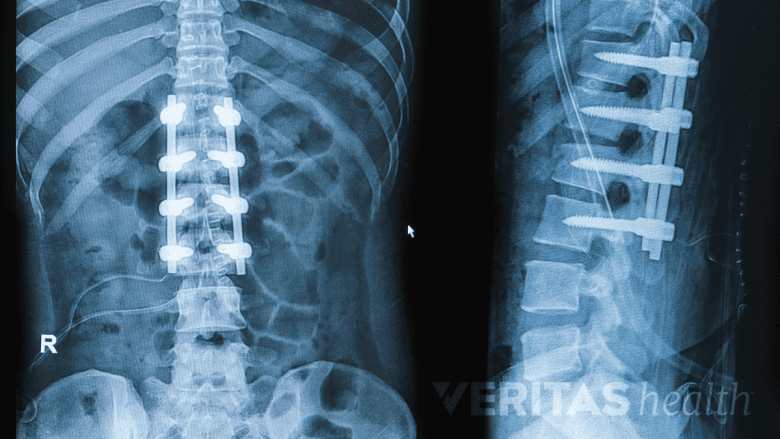

Fusion confirmed on an x-ray allows a full return to active life, including bending, lifting, and twisting.

Once the surgeon confirms on x-ray imaging that the fusion has completely solidified into one bone, a full return to an active lifestyle—including bending, lifting, and twisting—is permitted. This approval typically occurs about 6 months after the surgery, but sometimes it may take closer to 12 months.